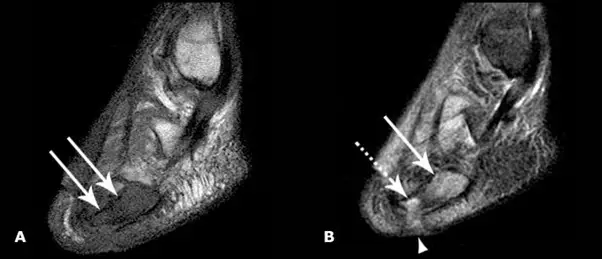

2. 同样病人的 MRI T1 相,j 箭头显示因为骨髓炎继发的水肿导致骨髓密度降低 B. 同一病人的 T2-相骨髓高密度,j 箭头显示皮肤溃疡,虚线箭头显示软组织增生;